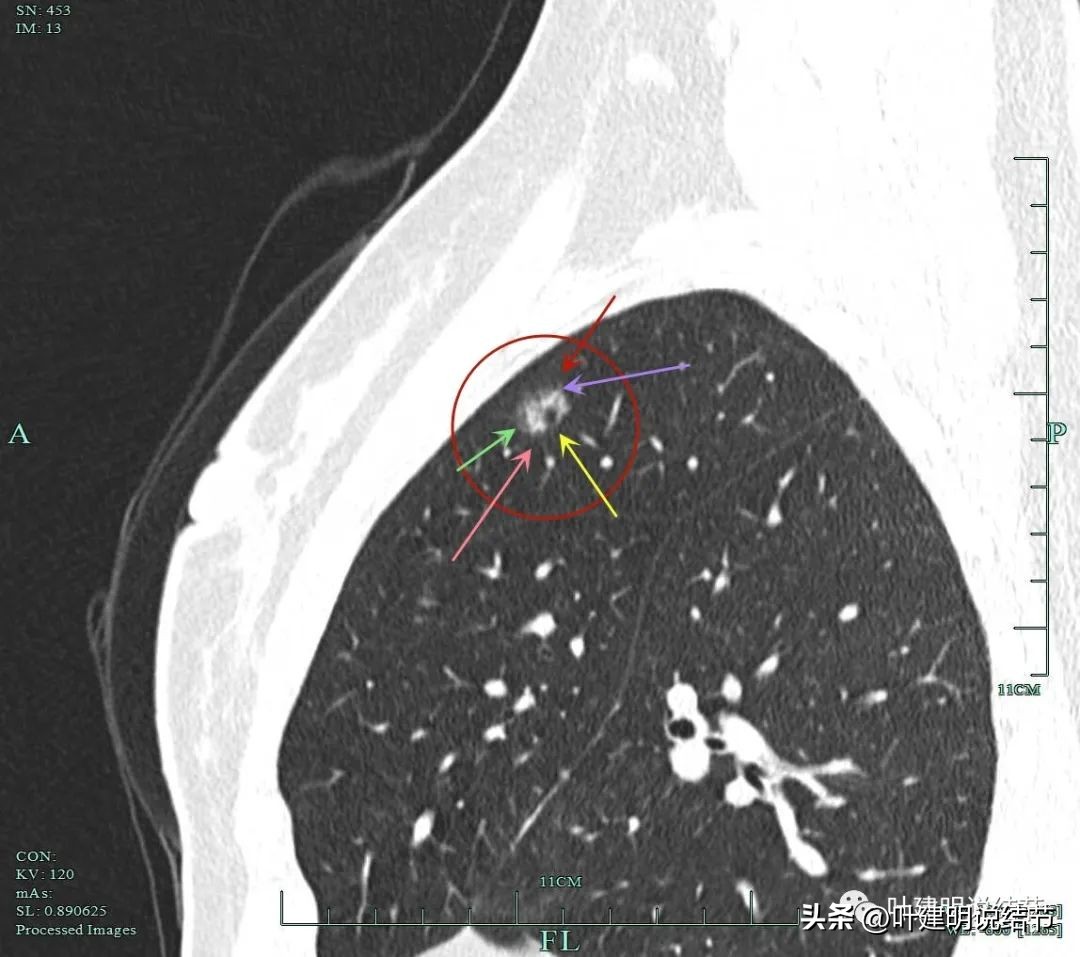

黄色箭头示病灶处有空腔征;粉色箭头示病灶内有实性成分;紫色箭头示毛刺征;绿色箭头示磨玻璃成分轮廓清,有毛刺。

砖色箭头示病灶有分叶征;蓝色箭头示胸膜牵拉;紫色箭头示毛刺征;红色箭头示整体轮廓与瘤肺边界清。总体上看病灶有收缩力、有分叶与毛刺,而且灶内密度不均。是较为典型的浸润性腺癌影像表现。

病灶毛刺、边界、空泡、胸膜牵拉等征象。